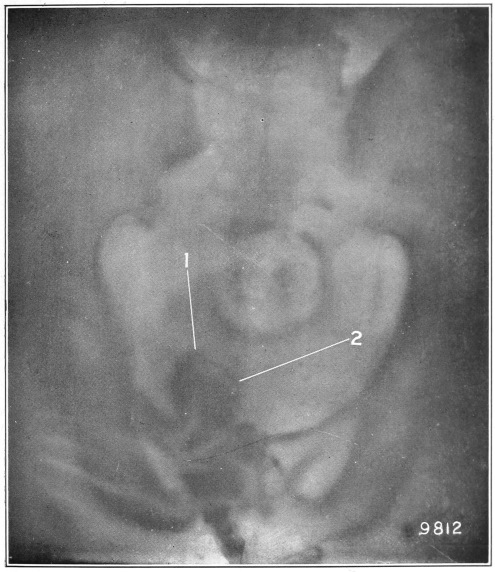

Nine Radiograph Illustrations Showing Mucus Channels and Cavities200

Fig. 4.

1, The dotted lines indicate the normal direction of the anus and rectum; 2, 4, the cavities or pouch formed by dilatation or ballooning from the storage of impacted feces; 3, a probe bent at right angles, and introduced through a speculum, to ascertain the depth of the pouch, which is frequently found to be two and a half inches.